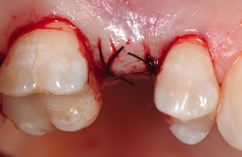

Unter Lokalanästhesie erfolgte nach krestaler Schnittführung die Aufklappung (Abb. 5) und die Aufbereitung des Implantatbettes gemäß dem chirurgischen Protokoll für NobelPearl mit den Bohrern des NobelPearl Surgical Tray. Nach Ankörnung mit dem Rosenbohrer wurde unter Beachtung der korrekten Implantatachse die 1. Bohrung mit dem zylindrischen Pilotbohrer Ø 2,3 mm auf die geplante Länge von 10 mm angelegt. Für die unterschiedlichen Längen stehen in der Folge formkongruente Profilbohrer zu Verfügung. So wird für die weitere Aufbereitung zunächst der Profilbohrer „small“, Länge 10 mm, Ø 3,3 mm (Farbcodierung violett), und danach der Profilbohrer „regular“, Länge 10 mm, Ø 4,2 mm (Farbcodierung gelb, hier mit Tiefenstopp), ausgewählt (Abb. 6).Da das NobelPearl-Implantat nicht selbstschneidend ist und beim Eindrehen des Implantats der Werkstoff Keramik keine Temperatur wie ein Titanimplantat ableitet, muss als letztes Instrument der Gewindeschneider auf die gesamte Implantatlänge eingesetzt werden.

Die Implantate wurden im Anschluss mit einer ausreichenden Primärstabilität von 30 Ncm und einem suprakrestalen Anteil 0,6 mm platziert. Diese suprakrestale Positionierung wird durch einen gegebenenfalls am Profilbohrer anbringbaren Tiefenstopp (Abb. 7) vereinfacht. Für das Einbringen der Implantate steht ein neues, zur „Inter-X“-Innenverbindung formschlüssiges Eindrehinstrument (Abb. 8) zu Verfügung, wodurch eine optimale Kraftübertragung während des Inserierens des Implantats gewährleistet wird (Abb. 9). Die Einheilkappen sind deutlich abgeflacht und ermöglichen einen einfachen primären Wundverschluss (Abb. 10 und 11). Im vorliegenden Fall verlief die Wundheilung komplikationslos. Nach einer auch für Keramikimplantate heute üblichen Einheilungszeit von 3 Monaten zeigten sich die Implantate in der Röntgenkontrollaufnahme stabil osseointegriert (Abb. 12). Es fanden sich an beiden Implantat-Loci entzündungsfreie Weichgewebsverhältnisse, woraufhin mit der prothetischen Versorgung des Implantats begonnen werden konnte.